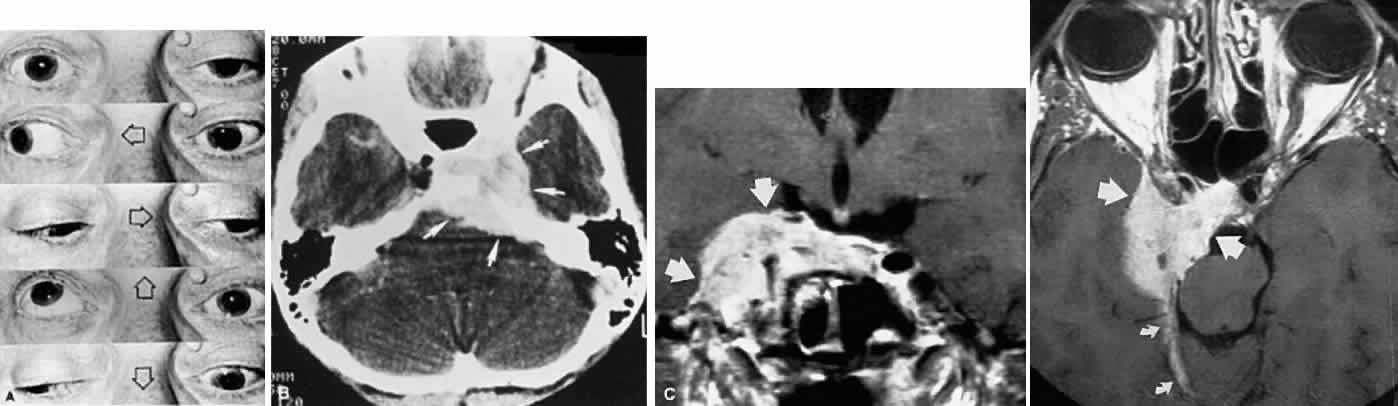

In the cavernous sinus, the abducens nerve may be involved in combination with the ophthalmic-trigeminal, third, or fourth nerves. Abducens monoparesis is frequent with cavernous sinus lesions, perhaps related to the nerve's location within the sinus, inferolateral to the carotid artery and unsupported by the dural wall of the sinus.19,20 Isolated abducens palsy occurs with carotid-cavernous fistulas (especially with spontaneous dural shunts21) and intracavernous aneurysms20 (Fig. 7), and is the earliest indication of contralateral spread of cavernous sinus thrombosis. Sixth nerve palsy accompanied only by ipsilateral Horner's syndrome also points to the cavernous sinus, since the ocular sympathetics from the carotid plexus may be simultaneously involved.22

Fig. 7. A. Chronic isolated sixth nerve palsy. B. Coronal and Axial (C) MRI sections showing large intracavernous internal carotid aneurysm (arrows).